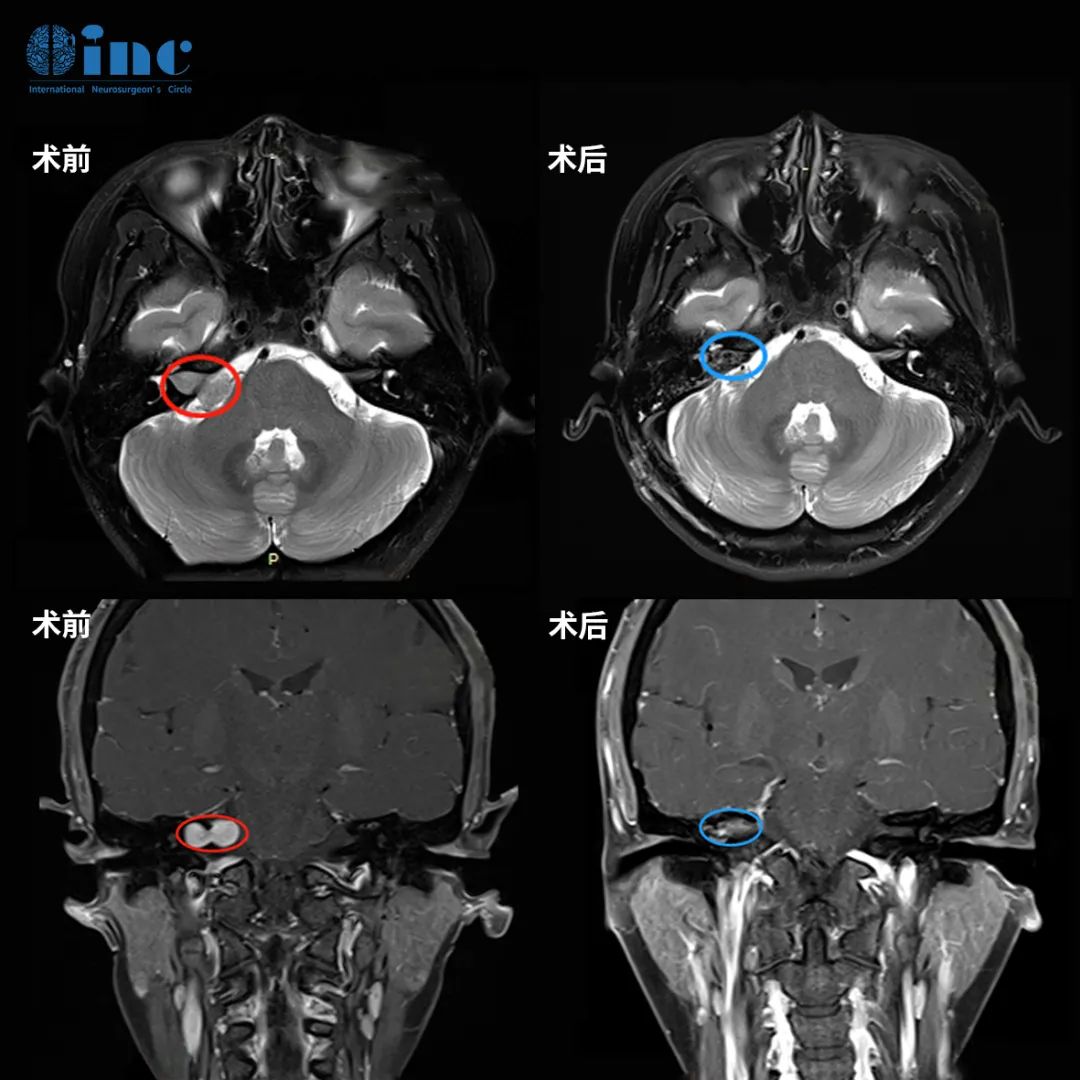

手术结果令人满意:肿瘤获得完全切除,面神经成功保留,未发生面瘫并发症。姜女士苏醒后首先确认了自己的面部功能,当发现一切正常时,心中的重负终于卸下。